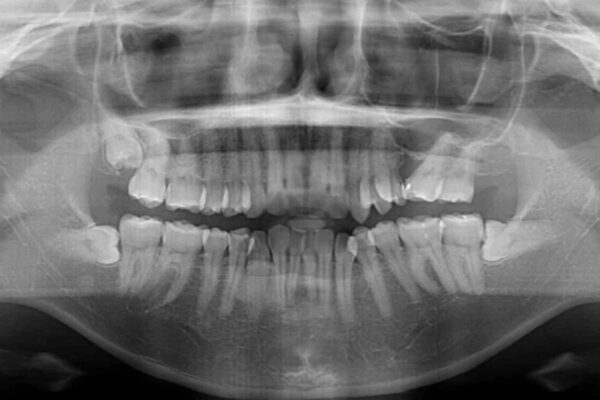

挺出歯を圧下してスペースを確保!目立たない部分矯正で下顎大臼歯にインプラント治療を実現

挺出歯を圧下してスペースを確保!目立たない部分矯正で下顎大臼歯にインプラント治療を実現 ビフォー 挺出歯を圧下してスペースを確保!目立たない部分矯正で下顎大臼歯にインプラント治療を実現 アフター

「1年前に抜歯した右下の奥歯にインプラントを入れたい」とのことで来院されました。